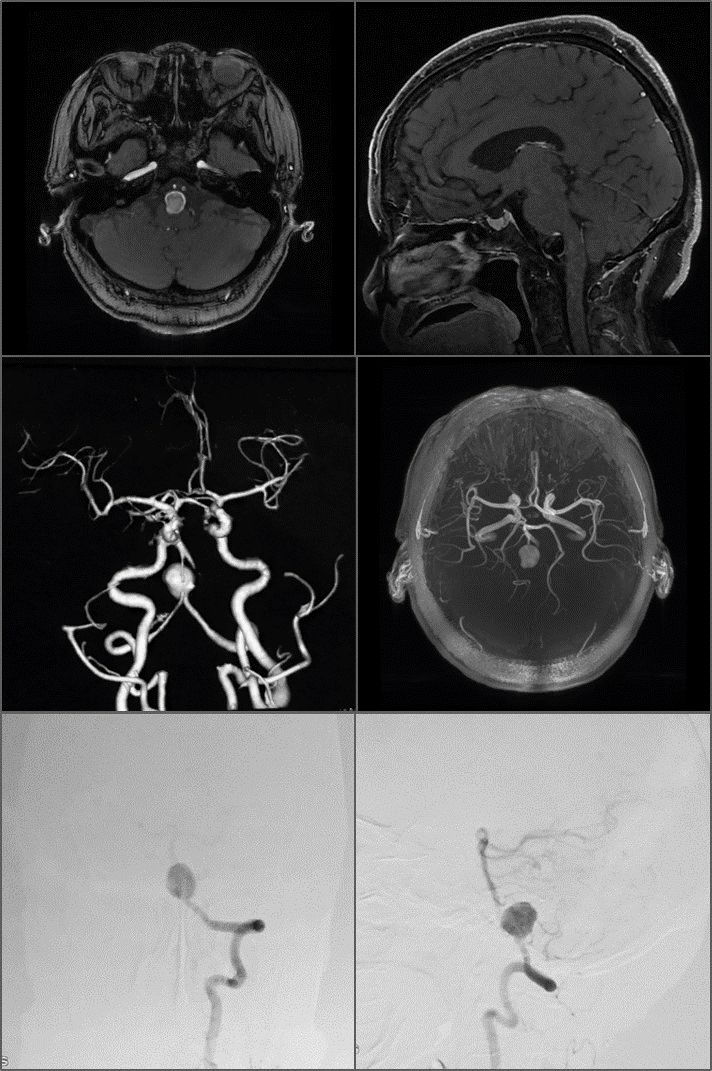

患者为一名67岁女性,入院17天前因突发头晕一次入院。患者患病以来无头痛呕吐,无抽搐,无意识障碍。入院体格检查神清语利,GCS15分,双侧瞳孔等大等圆,眼球运动佳,视力视野正常,余颅神经未见明显异常。术前CT,MR及DSA提示:左椎动脉夹层动脉瘤累及小脑后下动脉,双侧锁骨下动脉及双侧椎动脉开口处极度迂曲。对于此类复杂动脉瘤,术者术前进行了详尽的计划,确定了复合手术下动脉瘤孤立及枕动脉-小脑后下动脉端侧吻合的手术治疗方案。首先术前穿刺右侧股动脉留置造影导管备用,术中Doppler超声、ICG造影提示动脉瘤闭塞,PICA血流通畅,继而术中DSA造影,证实动脉瘤不再显影,桥血管通畅。

术前MRI、MRA及DSA提示:左椎动脉夹层动脉瘤累及小脑后下动脉,双侧锁骨下动脉及双侧椎动脉开口处极度迂曲。